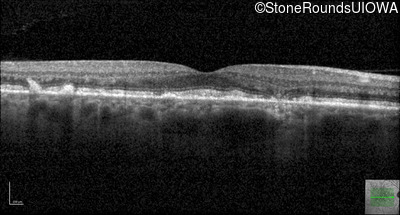

Optical Coherence Tomography - Right - 20/20 -1 sc

Exemplar / OCT Stack